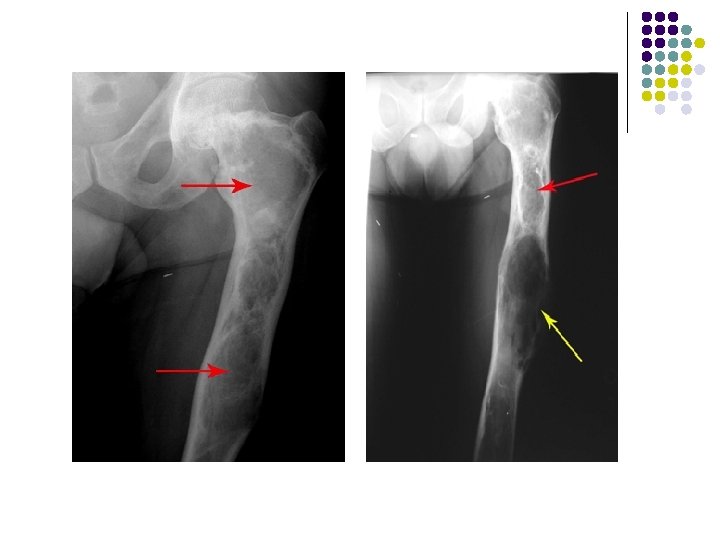

PLAIN RADIOGRAPH l l l l Expansile , Solitary lytic bone lesion Closed epiphyses No reactive sclerosis /No periosteal reaction May break through cortex with cortical thinning Soft-tissue invasion (25%) Pathologic fracture (5%) May cross joint space in long bones (exceedingly rare)

AP radiograph of the left wrist shows an expanded solitary lytic lesion involving closed epiphyses subarticular position of the distal ulna without rim of sclerosis or periosteal reaction which is typical for a giant cell tumor

Giant cell tumor of distal radius is eccentric and extend to the end of the bone